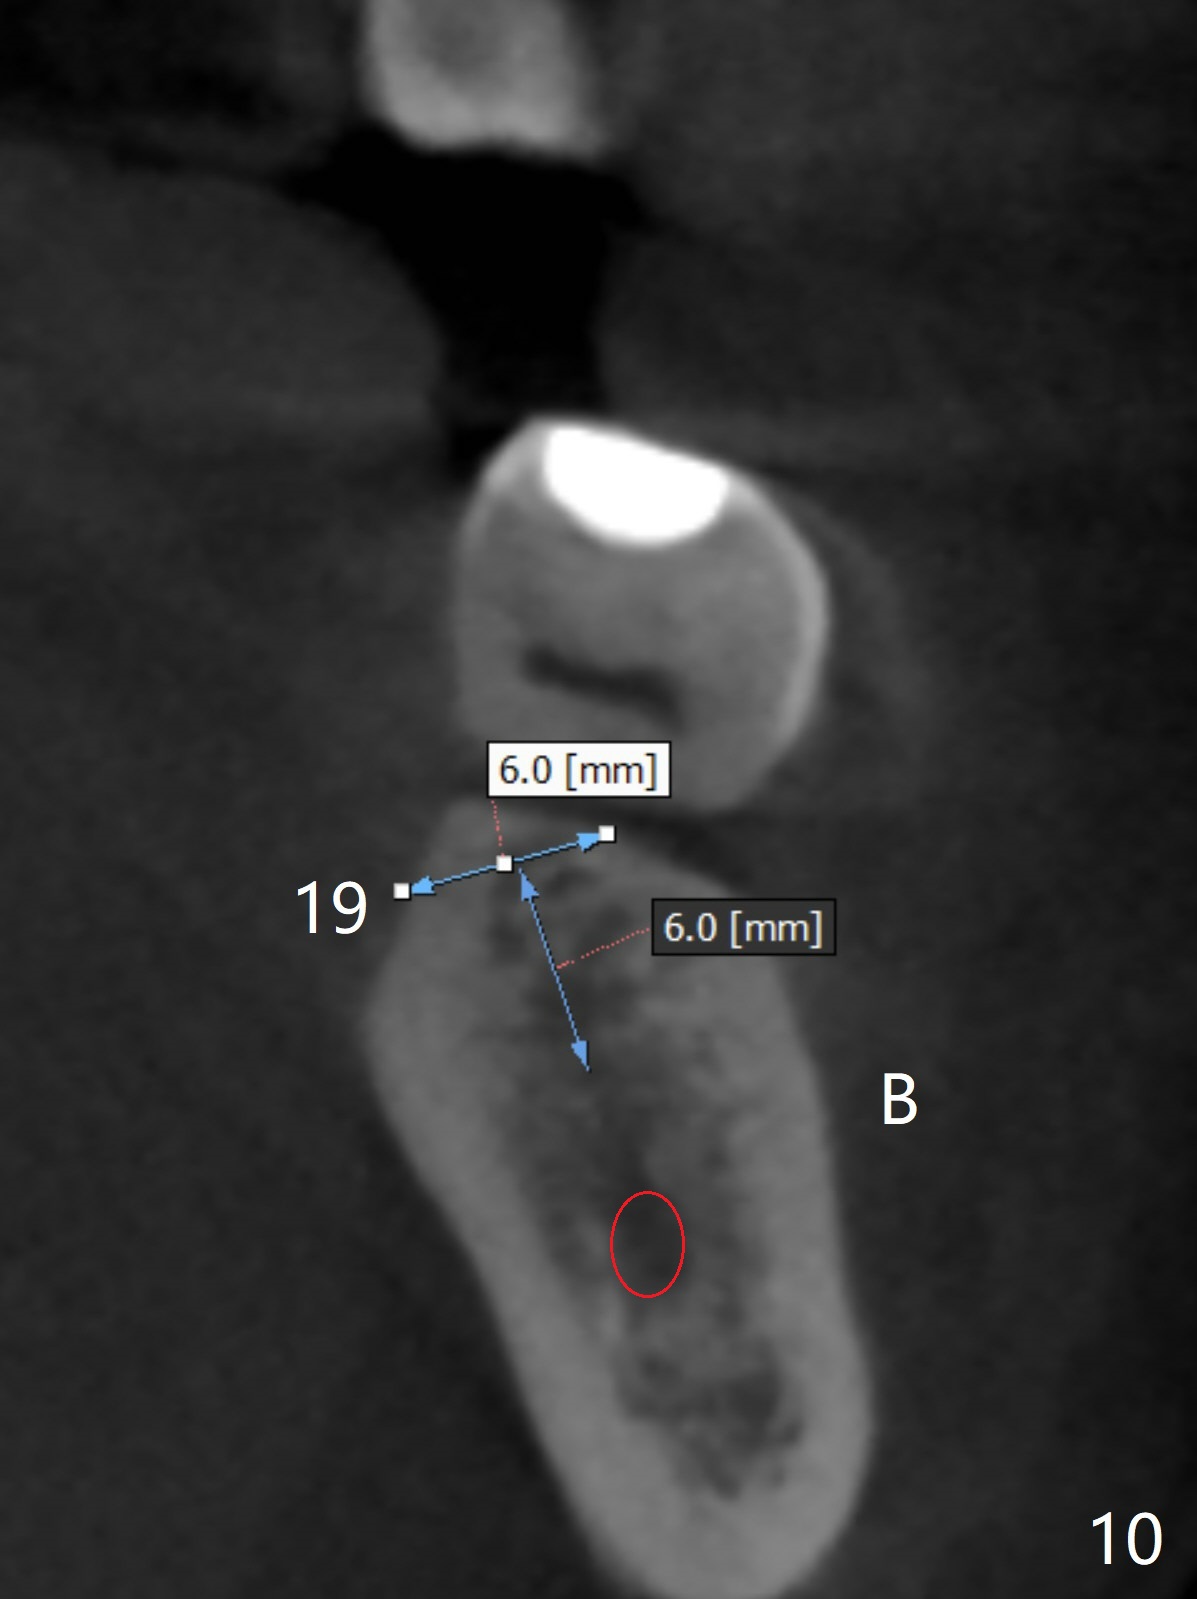

A 43-year-old man has poor dentition on the left: 1st molar missing, 2nd molar mesial inclination (Fig.1) and 2nd bicuspid lingual tilt (Fig.2). The latter is nonfunctional (Fig.3 (linguoposterior view). Two molar implants will be placed in a position so that their crowns will be in cross bite (Fig.4,5), the same occlusal scheme as the teeth #21 and 22. When these implants osteointegrate, the provisional crowns (Fig.6 P) will be supraocclusal so that there is clearance (*) for #20 to upright orthodontically (Fig.7-9). Moreover, these implants will be used anchorage as well as #21 and 22. Panoramic X-ray (Fig.1) and CBCT (Fig.10-12) show limited bone height at the sites of #18 and 19. It appears that 5x8 and 5.9x6 mm implants are appropriate with ridge reduction at #19.